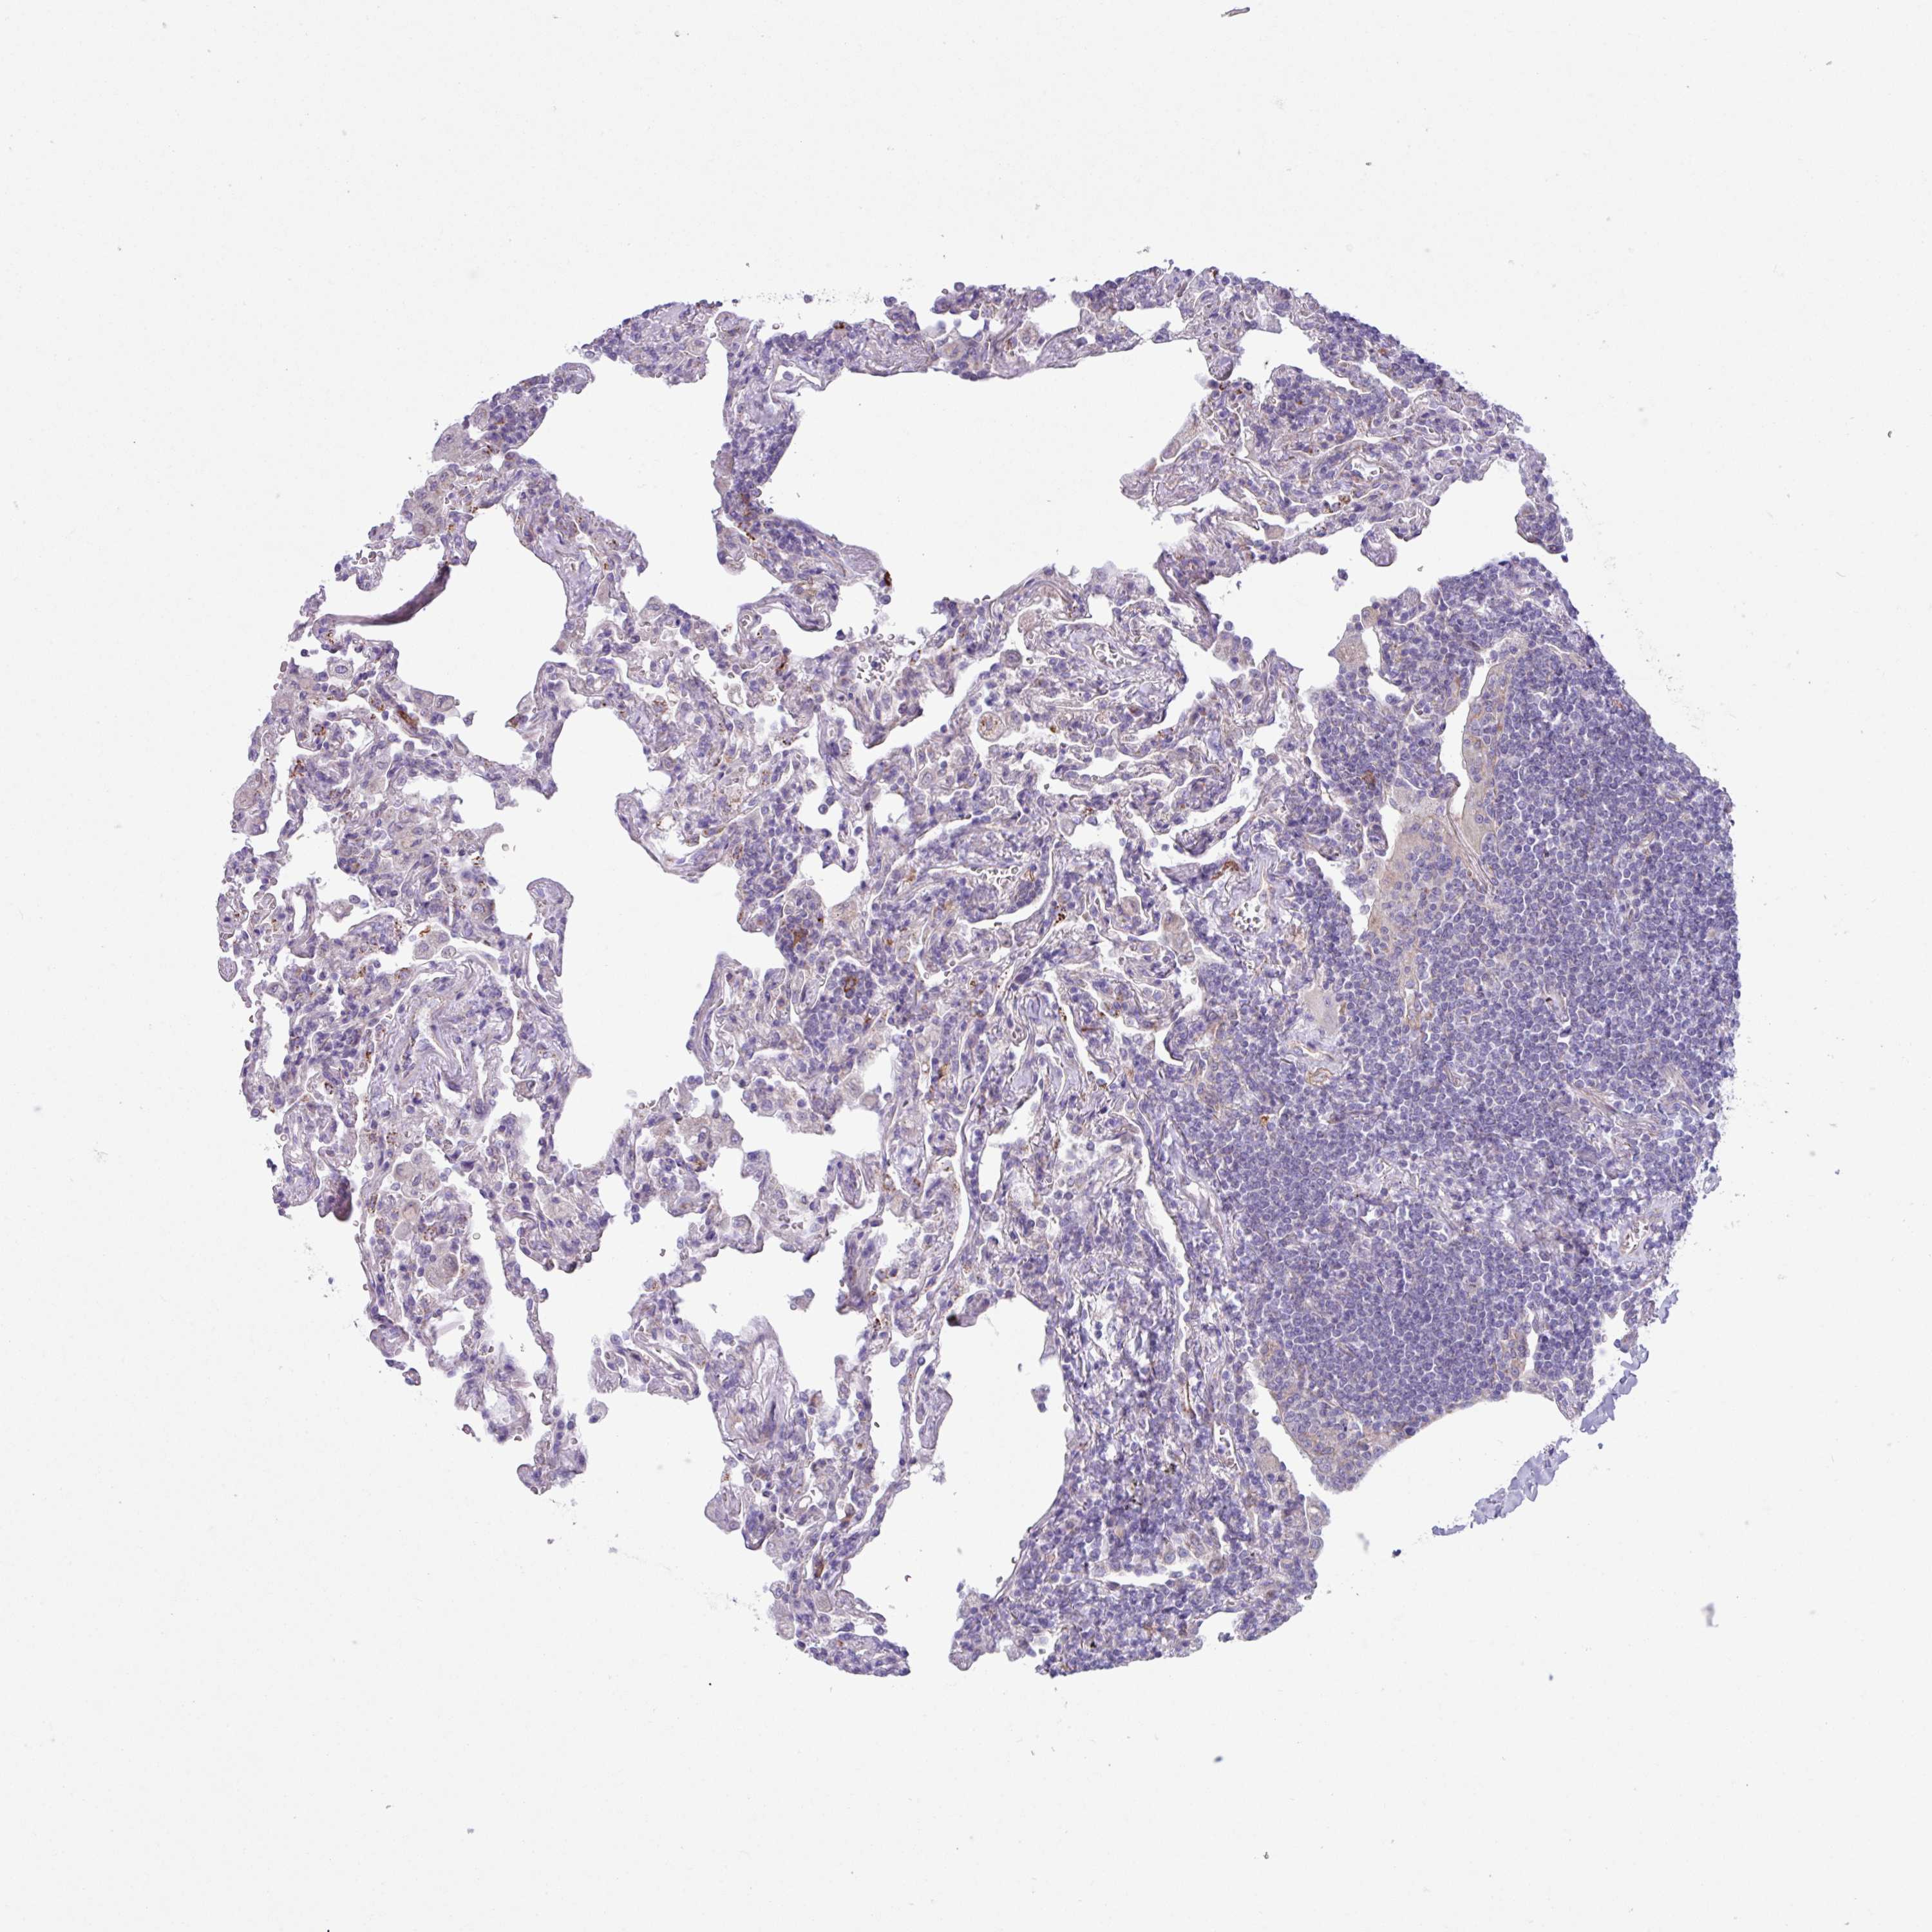

LYMPHOMA - Protein expressioni

A mouse-over function shows sample information and annotation data. Click on an image to view it in a full screen mode. Samples can be filtered based on level of antibody staining by selecting one or several of the following categories: high, medium, low and not detected. The assay and annotation is described here.

Antibody stainingi

Antibody staining in the annotated cell types in the current human tissue is reported as not detected, low, medium, or high, based on conventional immunohistochemistry profiling in selected tissues. This score is based on the combination of the staining intensity and fraction of stained cells.

Each image is clickable and will lead to virtual microscopy that enables deeper exploration of all samples and also displays staining intensity scores, fraction scores and subcellular localization as well as patient and tissue information for each sample.

Antibody HPA051074

Staining

High

Medium

Low

Not detected

Intensity

Strong

Moderate

Weak

Negative

Quantity

>75%

75%-25%

<25%

None

Location

Nuclear

Cytoplasmic/membranous

Cytoplasmic/membranous,nuclear

Malignant lymphoma, non-Hodgkin's type, High grade